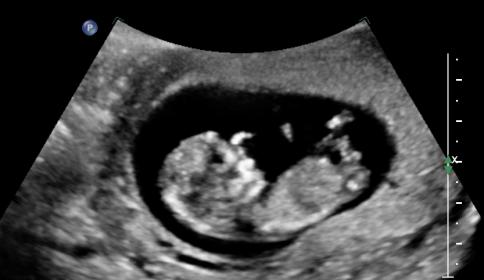

Attachment 7497Attachment 7498Attachment 7499

pic 3 made me lean boy.

I'd guess boy! Similar to my nub for this baby boy